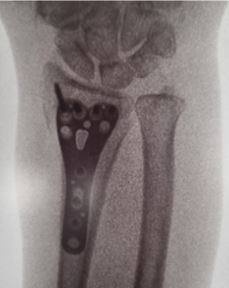

Plate and screw fixation of the wrist

A titanium plate is inserted across the wrist fracture and stabilised with screws.